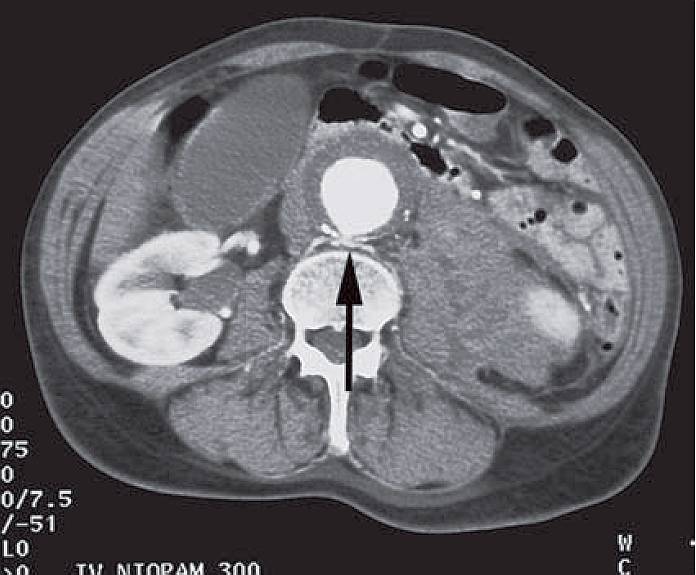

This patient underwent a CT scan. What does it show and what is the diagnosis?

The CT scan shows a 6 cm abdominal aortic aneurysm with a rind of thrombus (called mural thrombus) around the lumen, which is white due to the administration of contrast medium. The rind is deficient posteriorly, the site of a rupture (arrowed).

There is extensive haemorrhage around the lower pole of the left kidney and the descending colon is seen displaced posterolaterally around the haematoma. She has suffered a ruptured abdominal aneurysm with a contained retroperitoneal haematoma.